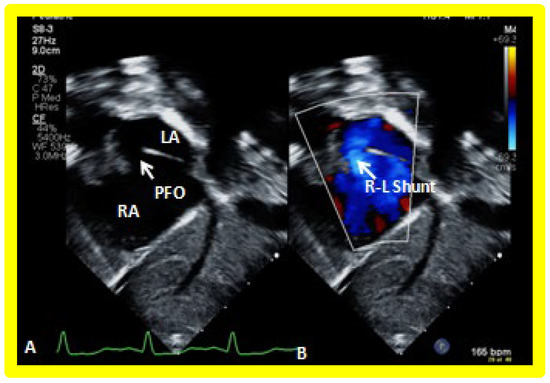

Following the demonstration of the atretic tricuspid valve, the sizes of the cardiac chambers are evaluated both by M-mode (Z scores) and 2D echocardiography; an enlarged RA, LA and LV and a small RV are seen (Figure 4, Figure 5 and Figure 6). Pulsed (not shown) and color Doppler (Figure 9) studies are helpful in illustrating right to left shunt across a PFO or an ASD.

Echo-Doppler studies should examine the adequacy of PFO/ASD to decompress the RA and allow unrestricted flow across it. In the majority of TA patients, the PFO/ASD remains wide open with unrestricted right to left shunt across it with laminar flow (Figure 18). This appears to be secondary to the persistence of fetal circulatory pathways. Only rarely does significant obstruction requiring intervention develop.

Figure 18. Selected video frames from a subcostal echocardiographic study demonstrating patent foramen ovale (PFO) (arrow in (A)) with right to left shunt (R-L Shunt) across the PFO (arrow in (B)). Note laminar flow across the PFO in B. LA, left atrium, RA, right atrium.